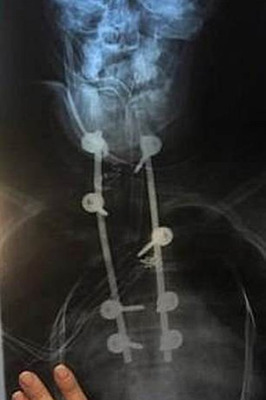

«Сфоткала свою новую спину после лечения сколиоза»

Привет! Мне сделали операцию по установлению металлической конструкции за 2 месяца до 18 летия, тоже был сколиоз. Сейчас мне 20 лет и я понимаю, что это было одно из лучших решений в моей жизни! Я больше не стесняюсь своей спины, она не болит и у меня прекрасная осанка :) Не бойся, что операция поставит крест на твоей жизни. Если корсет не поможет убрать градус, то не бойся операции. Все будет хорошо!

Здравствуйте! Операция была в четверг, я пролежала в реанимации 3 дня, в воскресенье меня перевели в палату, и сразу же поставили на ноги, в понедельник я уже сама вышла во двор ( нужно было спуститься по лестнице, пройти по отделению, то есть расстояние большое), и с каждым днем я все больше могла пройти, без надобности прилечь. Через 3 недели после операции, уже могла гулять километра 2 без особых трудностей. Через месяца полтора, я уже жила обычной жизнью, из ограничений я уставала больше, чем до операции, нужно было привыкнуть к новому положению спины, были небольшие трудности с балансом в пространстве, поэтому гулять ходила только с кем то. Сейчас прошло чуть больше 2 лет после операции, и ограничений по сути нет (ну нельзя прыгать с парашютом и кататься на американских горках)) И я стала более активной в повседневной жизни тк ушли комплексы, перестала болеть спина, я наконец таки смогла носить ту одежду которая мне нравится, а не мешковатые футболки, которые скрывали реберный горб. У меня сейчас полностью ровная спина ( осталось 5 градусов, а порог с которого отсчитывают врачи первую стадию сколиоза 7 градусов). Я надеюсь, что понятно написала, потому что у меня привычка сумбурно писать. Можете еще задать интересующие вопросы. Я с радостью отвечу! :)

А разве сколиоз оперируют??? Шрам знатный...

Ну как оперируют... Выравнивают стержнями, потом удаляют их.

Сколиоз оперируют. Британская принцесса Евгения показала свои рентгеновские снимки в поддержку людей с этим диагнозом, и свадебное платье выбрала, не скрывающее шрам после операции.

Оперировали и раньше. Уже лет 40-50 оперируют

19 век первые операции, с 1960х развивают разные протоколы для разных видов сколиоза. На самом деле в рамках истории считайте вчера начали.